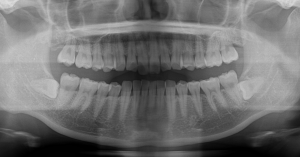

5.親知らずによって歯並びが押されている場合には抜歯が必要なことがあります。

後方から押してくるような場合や横向きで明らかにまっすぐに生えてこないような親知らずは抜歯を行った方がベターです。当院では親知らずに関しては大学病院の口腔外科勤務の口腔外科専門医が勤務しておりますので安心安全を最優先に抜歯を行っております。